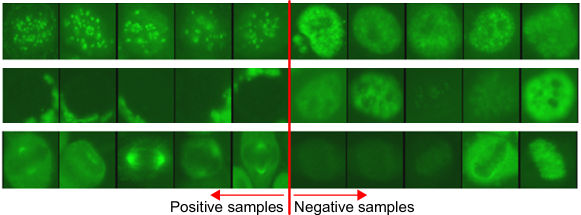

Contributions The aim of the present work is to devise an algorithm which learns image descriptors for ANA IIF specimen image classification problem with three properties: (1) highly discriminative; (2) semantically meaningful at cell level and (3) having short descriptor length. We achieve this by proposing two learning schemes for discovering cell-level attributes through a discriminative learning framework. In contrast to previous approaches [1, 16] which learns discriminative image-level attributes, our approach learns cell-level attributes where their values can be used to construct discriminative image-level descriptors. Our theoretical results show that under a certain condition, it is possible to devise solutions based on image-level discriminative attribute learning for solving the posed problem. Finally, we further showcase (refer to Fig. 1 for some examples of discovered meaningful cell attributes) that a textual description can be generated from the learned cell-level attributes and shares similarities to the description from experts. We evaluated all the approaches on the new HEp-2 cell dataset proposed for the specimen image classification problem. To our knowledge this is the first comprehensive dataset constructed for this purpose.

We first selected the most frequently appearing cell-level attributes from each pattern. From the selected set, we further excluded the attributes which appear in at least more than four classes. Finally, to name the cell attributes, we presented each cell attribute to the domain experts who were trained to read ANA by showing them both images classified as positive and negative by the attribute classifier. We note that we presented the cell images in green colour which is similar to the colour of an ANA specimen under a fluorescent microscope. Since the attributes are extracted from each cell region, we could ask more specific questions to the experts in relation to each region (e.g. Please describe the property appearing at the cell boundary). The experts could opt not to name an attribute if they were not able to find any consistent property in the positive cell images. Fig. 5 and 1 present some examples of cell attributes successfully identified by the experts.